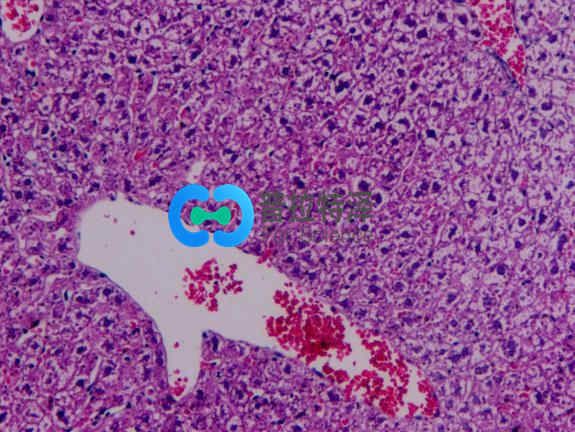

光鏡觀察:

正常組肝小結構正常,肝細胞以中央靜脈為中心呈放射狀排列。無肝細胞腫脹及脂肪變性。模型組肝組織HE染色顯示:造模4周后大鼠肝臟即有輕微的肝細胞脂肪變性,標本還出現匯管區及小葉內炎癥細胞浸潤和散在的點狀壞死;造模8周大鼠多呈中度脂肪變,且炎癥活動積分明顯高于造模4~8 周大鼠,可見到小葉內炎癥,炎癥細胞主要以單核細胞為主,炎癥程度明顯加重;造模 18周大鼠呈中重度的大泡性脂肪變,脂滴分布密度通大,可見大部分旺細胞漿含大脂滴,部分脂滴形成大空泡。將細胞核擠壓至一邊,目以中央靜脈周圍為其:肝小葉結構破壞,肝細胞排列不規救,并伴大量肝細胞腫脹,部分呈氣球樣變,匯管區炎癥尚輕微。